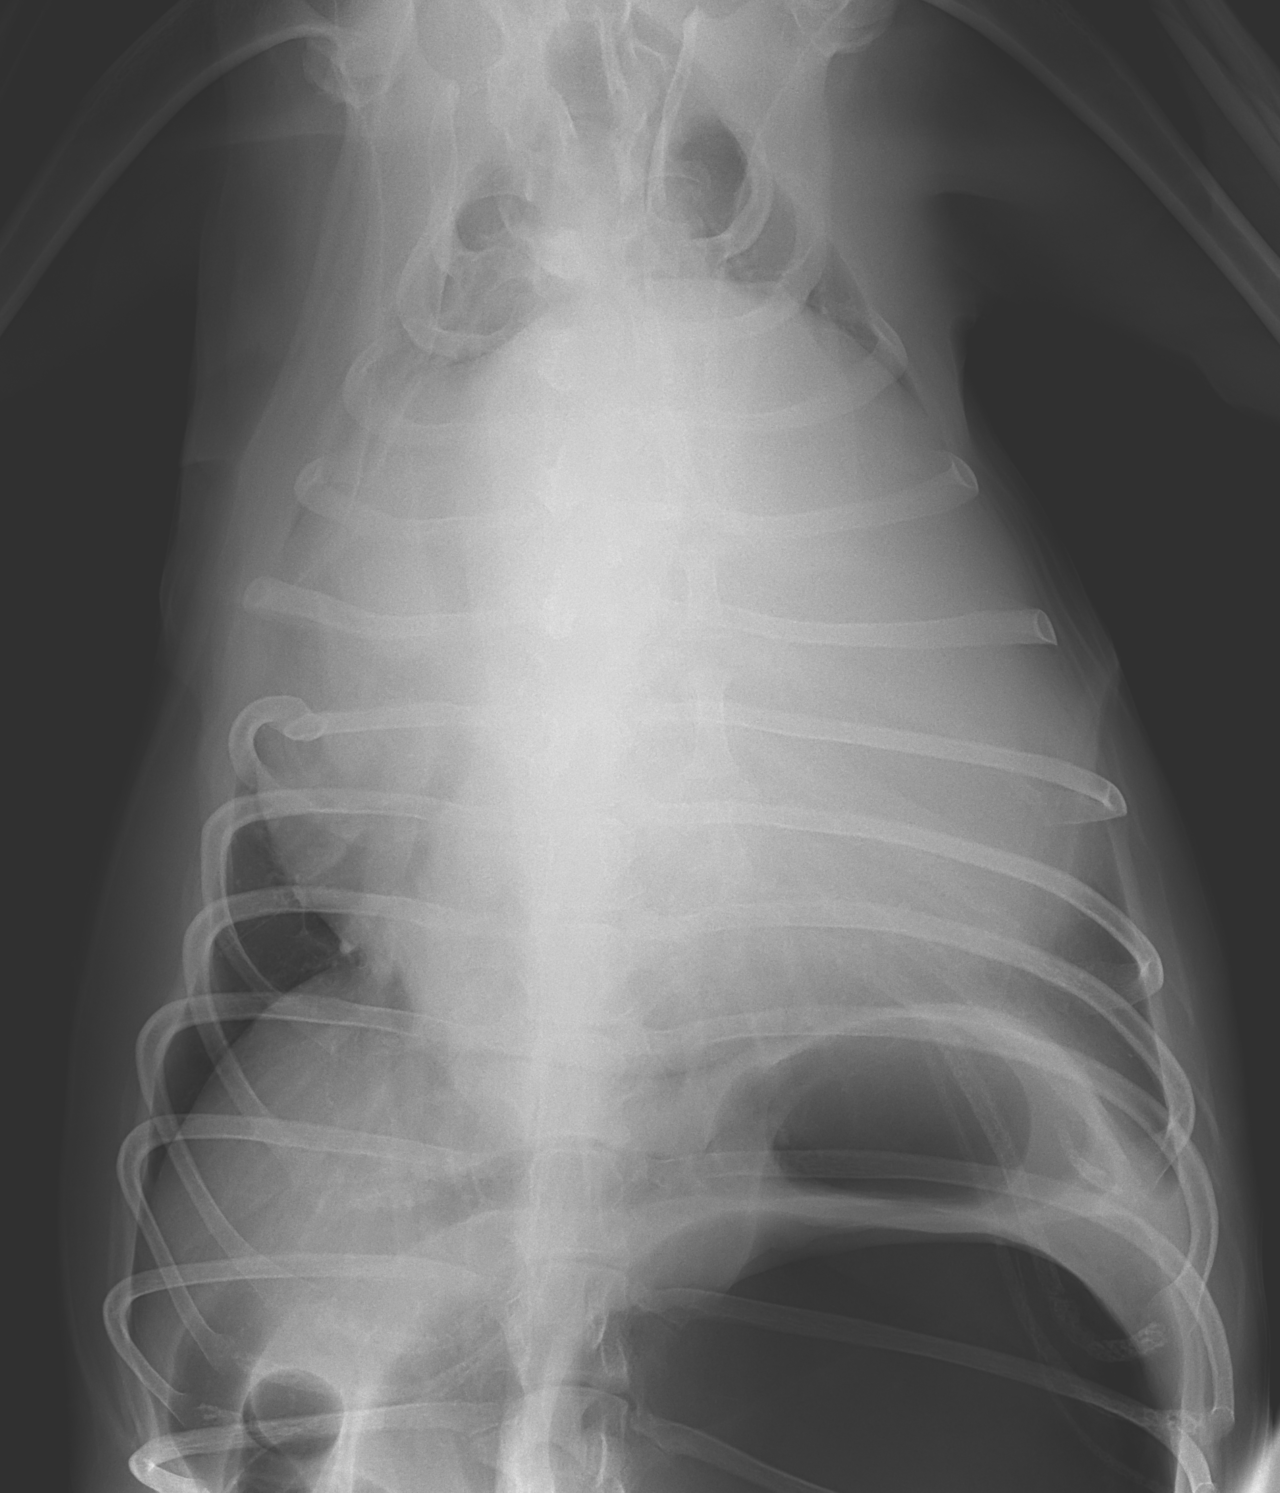

高齢(12歳)のアフガンハウンドが吐きたそうだけど、何も出てこない。次第に起立出来なくなったとのことで夜間に救急で来院しました。症状とエックス線検査から胃捻転と診断しました。また聴診時に心音は遠く、聴取出来ませんでした。胸部エックス線検査においてムーンハートが確認されました。超音波ガイドで出血性心のう水を2リットル抜去しました。バイタルサインが落ち着いたところで胃捻転整復術を実施しました。その後も出血性心のう水は貯留傾向にありました。高齢であることから血管肉腫が疑われましたが、各種画像診断においても腫瘤の存在はなくまた細胞診においても血管肉腫の可能性は低いものと判断しました。胃捻転から2週間後、心膜の生検と再発性の心膜貯留を回避する目的で心膜切除術を実施しました。心膜は顕著に肥厚し、線維化を伴っていました。病理検査の結果をもとに内科療法を併用する予定です。高齢ながら頑張ってくれました。